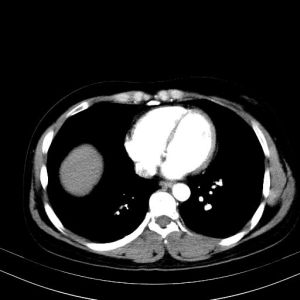

2.CT表現:

(1)平掃:肝內低密度或等密度占位性病變,出血、鈣化可為不規則高密度,邊緣光滑,周圍可見“透明環”影,常為特徵性表現。病理基礎一般為是由瘤周被擠壓的肝細胞內脂肪空泡增加而致。

(2)增強:早期可見均勻性增強,之後,密度下降與正常肝組織呈等密度。晚期呈低密度。其瘤周之透明環無增強表現。

(3)腫瘤惡變可呈大的分葉狀腫塊或大的環死區,偶爾可見鈣化。

輔助檢查

常規實驗室檢查對HCA的診斷無幫助,通常HCA患者的血細胞、肝功能在正常範圍內,HBsAg多陰性,AFP檢測絕大多數病例正常。影像學超聲檢查可見病灶邊界清晰,瘤內回聲不均,周邊有聲暈。HCA的CT典型表現是平掃為等密度或略低密度,增強掃描動脈期均明顯強化,門脈期呈略高或等密度影,延遲期為等密度。有時腺瘤表現不規則密度影可能與瘤內出血壞死有關。